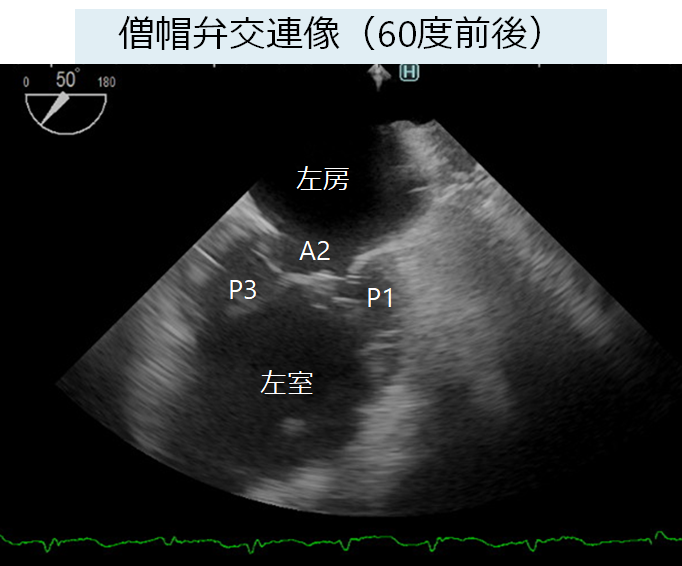

初心者から研修医向けの経食道心エコーに関する専門書。- タイトル: 経食道心エコー II- 監修: 野村 実- 定価: 12,500円ご覧いただきありがとうございます。数回読んだだけで非常にきれいな状態です。